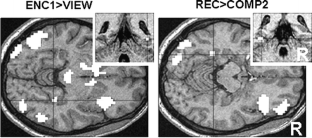

Using a declarative memory paradigm, the anatomical correlates of spatial location encoding and retrieval in the healthy human brain as reflected by BOLD fMRI were investigated. During encoding, subjects were instructed to view and keep in mind different locations of an object on a platform seen from different viewpoints in virtual 3D. In retrieval trials, subjects had to recognize previously learned object locations. Comparing activation patterns associated with encoding and recognition on a voxel-by-voxel basis, we found regions in the precuneus bilaterally activated by both processes. To our knowledge, this is the first study that directly compared human brain activation patterns associated with allocentric encoding and retrieval of spatial locations in virtual 3D. Our results provide further information concerning the role of the precuneus in declarative memory processes, pointing to precuneus involvement in encoding and retrieval of spatial locations.

Fig. 1

Fig. 2

Fig. 3